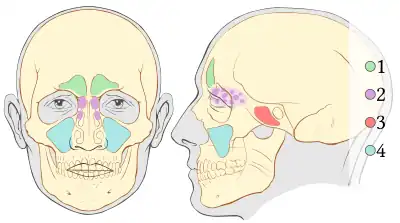

1. Stirnhöhle, (grün), (Sinus frontalis),

2. Siebbeinzellen, (lila), (Cellulae ethmoidales)

3. Keilbeinhöhle, (rot), (Sinus sphenoidalis)

4. Kieferhöhle, (blau), (Sinus maxillaris)

Im Oberkiefer erfolgt der Kieferaufbau analog dem des Unterkiefers mit Ausnahme des Bereichs der Oberkieferbackenzähne. Im Bereich der Zähne 15 – 17, bzw. 25 – 27 sind die Zahnfächer der Zähne (in der Regel) nur durch eine dünne Knochenlamelle, den Kieferhöhlenboden von der Kieferhöhle getrennt. Im Seitenzahnbereich des Oberkiefers erfolgt der Knochenabbau oft durch ein Absinken des Kieferhöhlenbodens bei weitgehend unveränderter äußerer Form des Alveolarkamms. Die Dicke des Kieferhöhlenbodens kann dabei bis zur Papierdicke reduziert werden. Um auch hier Implantate mit der entsprechenden Mindestlänge einbringen zu können, muss ein Knochenaufbau durchgeführt werden. Dieser erfolgt in der Regel durch einen Sinuslift.

Sinuslift

Zur Schaffung eines Implantatbetts im Seitenzahnbereich erfolgt der Knochenaufbau nicht durch Auflagerung von Knochen (oder Knochenersatzmaterialien) auf den Alveolarkamm, sondern gewissermaßen von innen, nämlich durch eine Auflagerung des Knochentransplantats auf den Kieferhöhlenboden unterhalb der Schneiderschen Membran, die die Kieferhöhle auskleidet. Damit erfolgt eine Verdickung des Knochens innerhalb der Kieferhöhle.